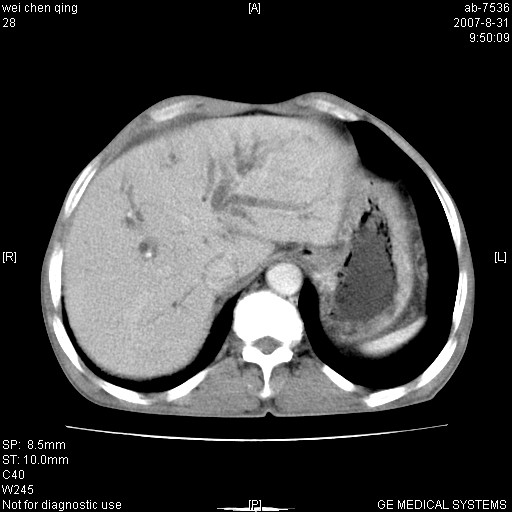

以下是引用zyyzzy在2007-8-31 14:34:00的发言:[br]该病人肝内胆管扩张,胆囊及胆总管未见明显扩张。在倒数第9层图像上可看到左右肝管结合部(肝总管)有软组织影,此处应薄层扫描。考虑肝总管占位(ca)、腹水。[br]